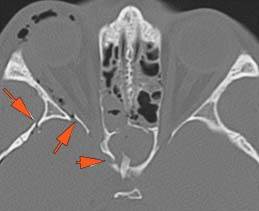

There is bony injury or displacement of the body, angle, ramus, parasymphyseal region, alveolar ridge, and condylar and coronoid process of the mandible. [In case of fracture, describe complexity and displacement]. [Yes/No]

There is condylar fracture either within or outside of the joint capsule, or with or without involvement of the articular surface of the condylar head. [Yes/No]

There is evidence of radiodense intra-articular osteochondral fragments. [Yes/No]

There is bony injury or displacement of the external auditory canal and/or other evidence of temporal bone injury. [Yes/No]